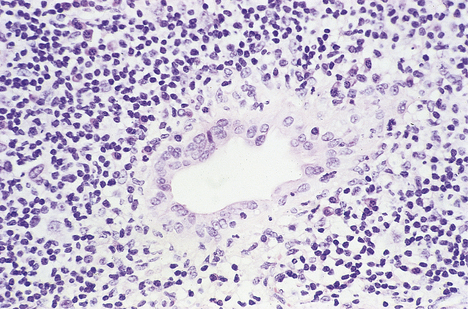

image

Fig. 16.5 Liver histology in acute viral hepatitis. There is disarray of the liver cell plates, accompanied by an inflammatory infiltrate and liver cell apoptosis (arrowed).

Although the pathogenesis of the liver cell damage resulting from HAV and HBV infection is different, the changes in the liver in a typical case are very similar (Fig. 16.5). The principal features are:

cytoplasmic swelling of liver cells

apoptotic death of individual liver cells

infiltration of portal tracts by mixed inflammatory cells and expansion by oedema

hyperplasia of Kupffer cells; in the later stages of the disease, during recovery, cellular debris (ceroid) accumulates in their cytoplasm

accumulation of bile in liver cells, which are often swollen, and within the intercellular canaliculi, where it is sometimes misleadingly referred to as ‘bile thrombi’; this pooling of bile within the liver cells and the canaliculi is called cholestasis.